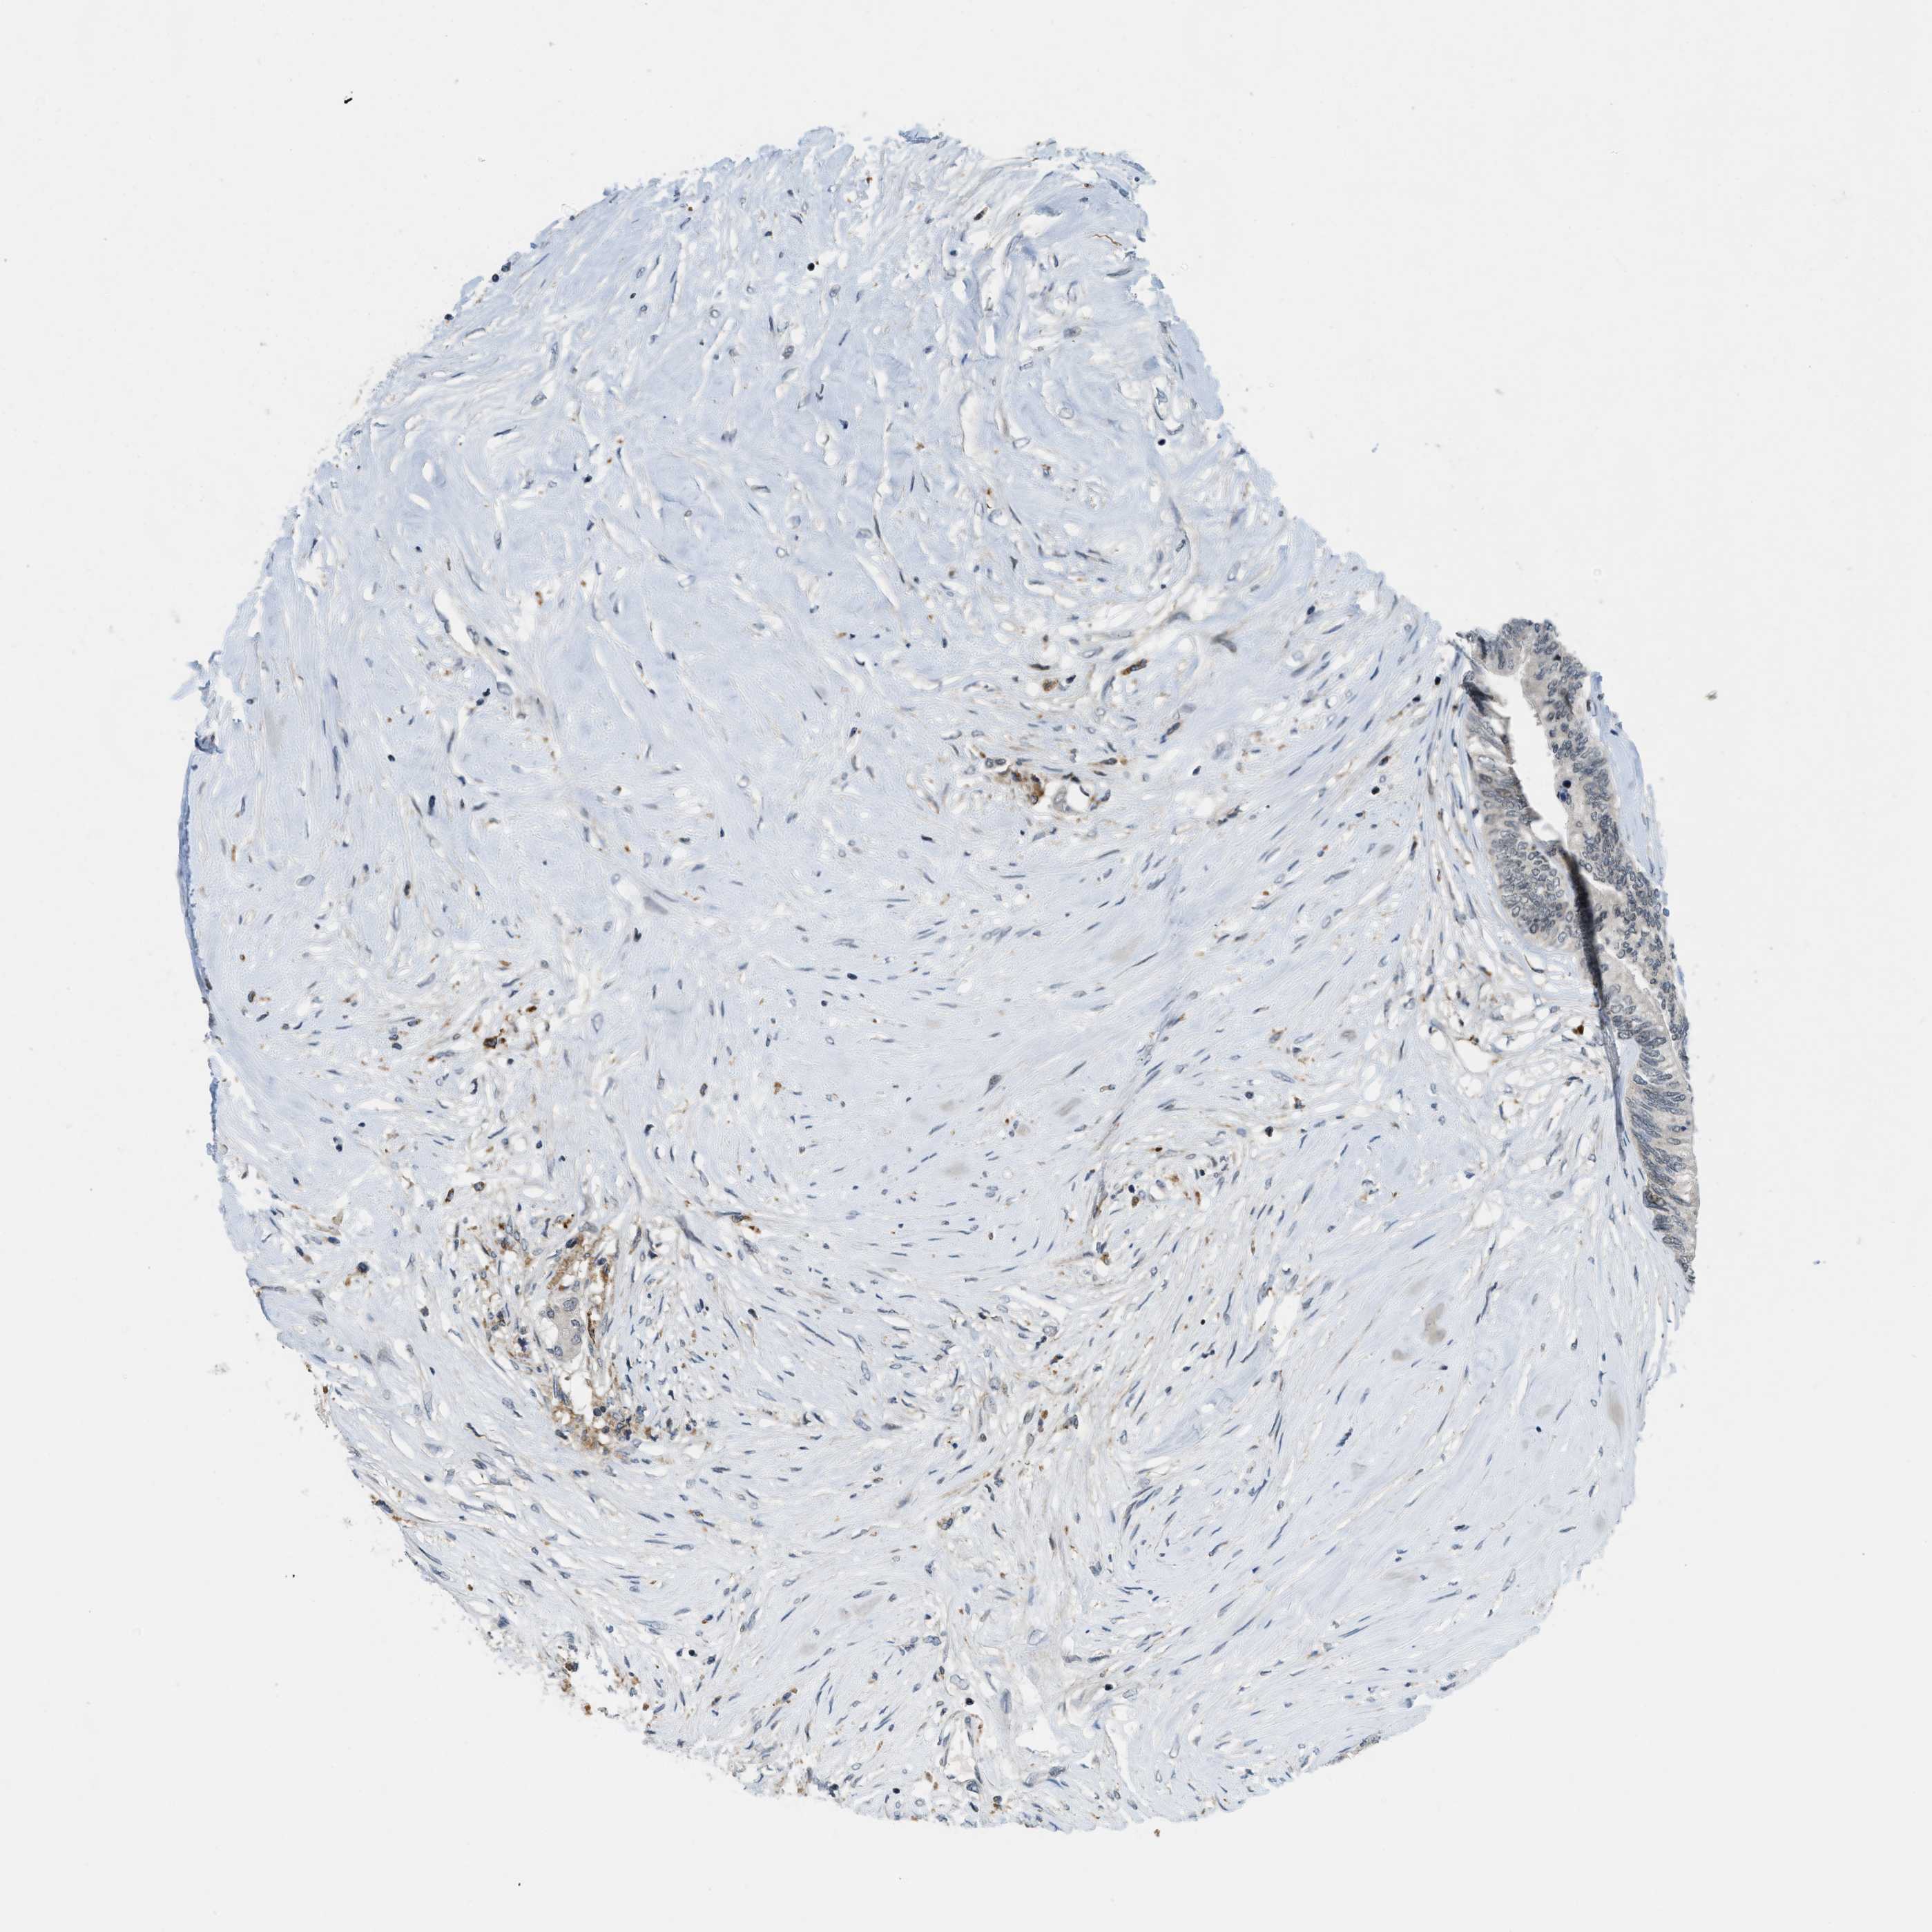

CANCER COLORECTAL CANCER Show tissue menu

COAD TCGA COAD VALIDATION READ TCGA READ VALIDATION PROTEIN COAD CPTAC PROTEIN EXPRESSION

ANTIBODIES

AND

VALIDATION